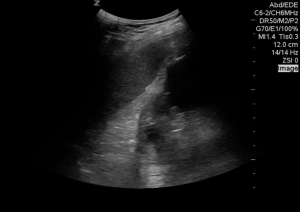

This is a view of a patient’s left upper quadrant, there is a hypoechoic area in the splenorenal interface.

…but is it free fluid?

Unless you have just been taken off the laparoscopy table, there is no open space in the peritoneum, only potential space. Fluid must wedge itself between organs and the parietal/ retro-peritoneum. It doesn’t make sense for it to just disappear or divert from a peritoneal organ, it should follow the contour of the organ and ultimately taper of creating a ‘pointy’ appearance like this:

On further investigation the area in the first image was found to be a large renal cyst, this is a short axis view of the same area…